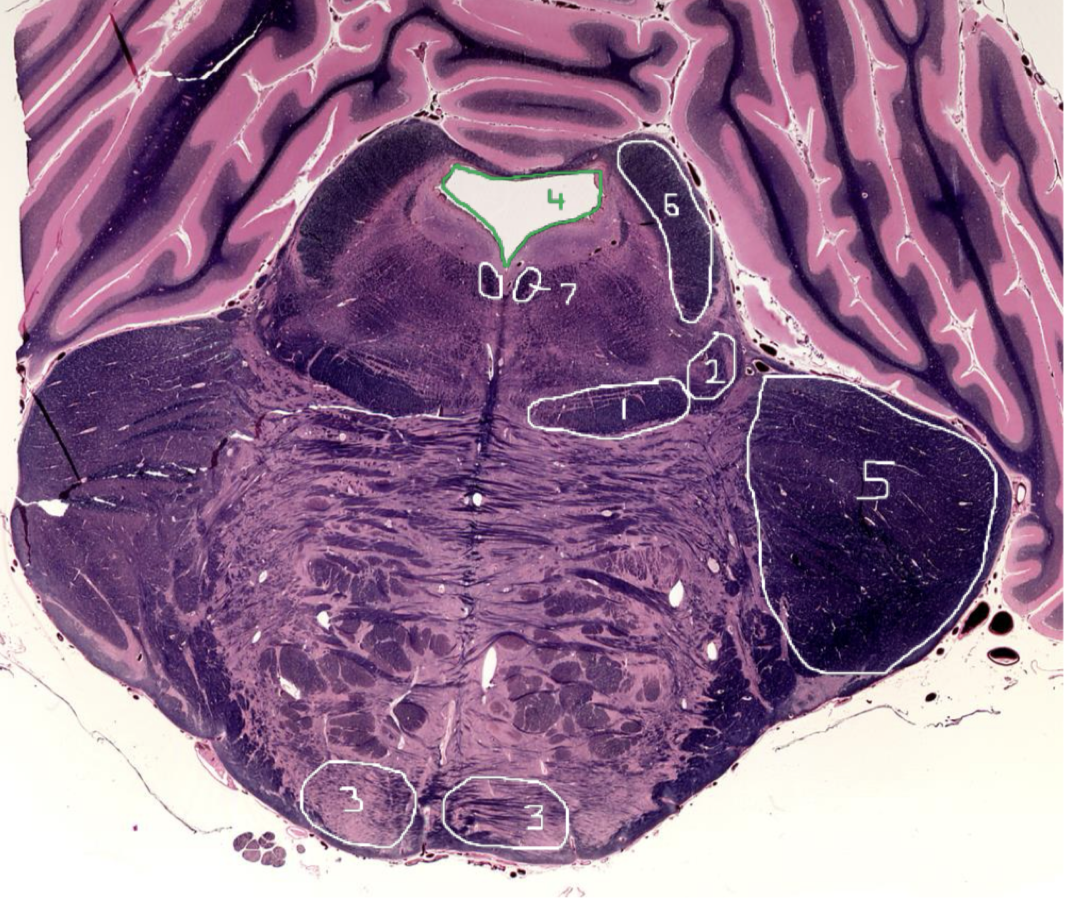

1

Medial Lemniscus - Rostral Pons

2

Spinothalamic Tract - Rostral Pons

3

CST - Rostral Pons

4

Cerebral Aqueduct - Rostral Pons

5

Middle Cerebellar Peduncle - Rostral Pons

6

Superior Cerebellar Peduncle - Rostral Pons

7

Medial Longitudinal Fasciculus (MLF) - Rostral Pons